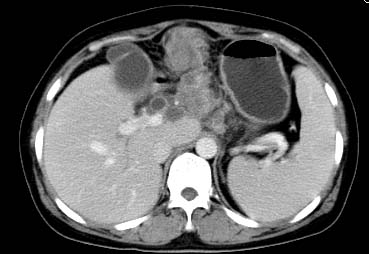

以下是引用西北一只狼在2008-6-30 20:58:00的发言:[br]肝左叶胆管细胞ca并肝门淋巴结转移、胰腺、胃小弯浸润

以下是引用ydx_74在2008-6-30 21:54:00的发言:[br]左叶胆管细胞ca并肝门淋巴结转移、胰腺、胃小弯浸润